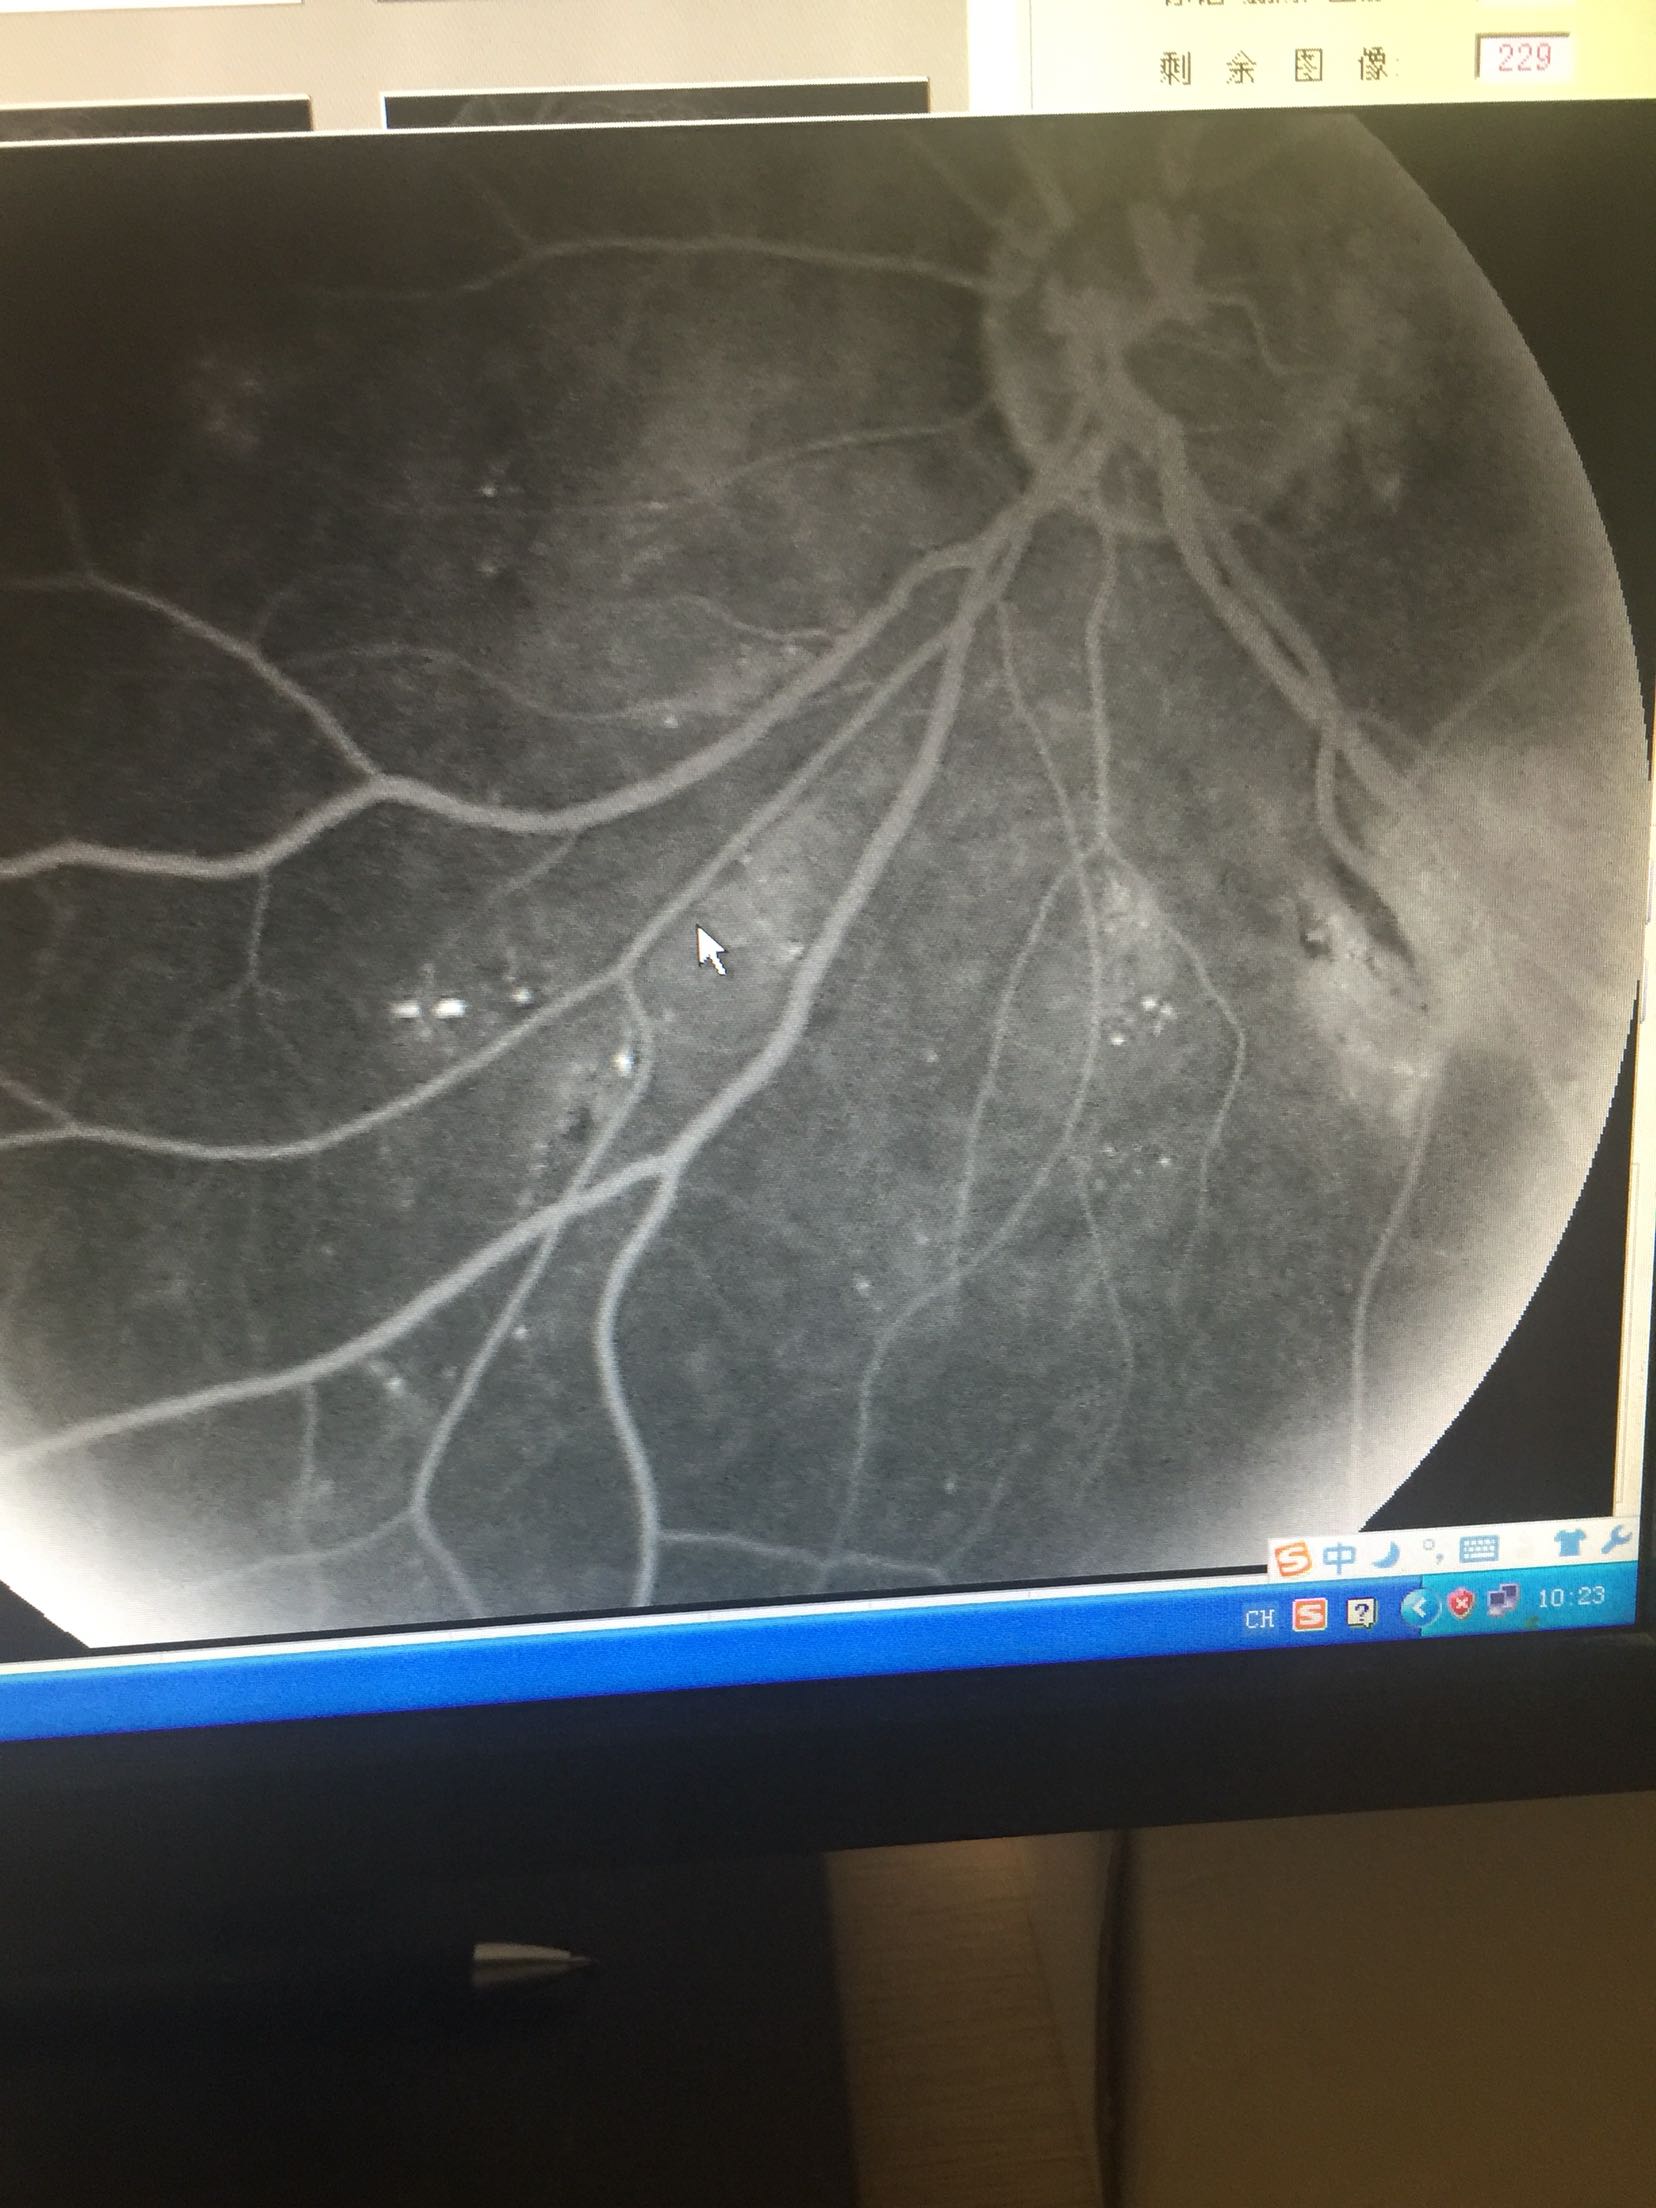

视力: 右眼0.6 左眼0.5 双眼睑无水肿,结膜无充血,角膜透明,前房正常,瞳孔圆,对光反射可,虹膜纹理清,晶体轻度浑浊,眼底视盘界清色可,黄斑区中心凹反光还可,网膜散在片状出血及硬性渗出 眼压:13/17 血压100/70mmhg 随机血糖:6.2

心电图:窦性心律,67次/分 造影:左眼动脉充盈时间为23秒,静脉充盈时间为27.2秒,双眼全视网膜可见片状荧光遮蔽及黄白色硬性渗出,早期双眼全视网膜散在点状高荧光,晚期有荧光渗漏

双眼糖尿病视网膜病变 药物促进血液吸收,改善眼底循环,视网膜光凝治疗